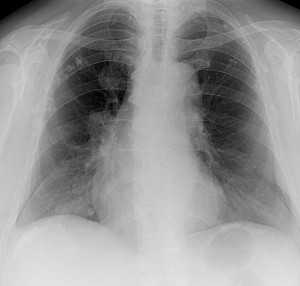

Метастазы в легких — фото рентгенограммы. Округлые тени — метастазы рака пищевода. Хорошо виден большой узел округлой формы вблизи переднего отрезка 2-го ребра. На снимке справа - циркулярное сужение пищевода за счет опухолевого утолщения его слизистой оболочки.

![image005]()

![image007]()

Как выглядят метастазы в легких на рентгене? Слева — узловые образования у пациента с раком яичка. Справа - метастазы рака яичников гематогенного характера с выраженным опухолевым лимфангиитом (обратите внимание на деформированный сетчатый, линейный характер легочного рисунка).